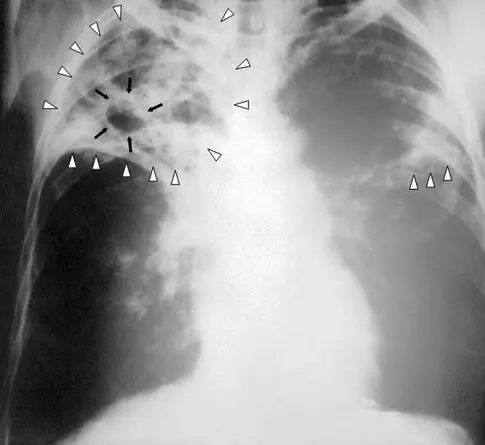

Key Information: Tuberculosis is transmitted through the air when infected individuals cough or speak. Authorities have assured the public that the overall risk is still minimal, but treatment entails a regimen of antibiotics lasting 4-9 months. Common early symptoms include a persistent cough, chest pain, and fever.